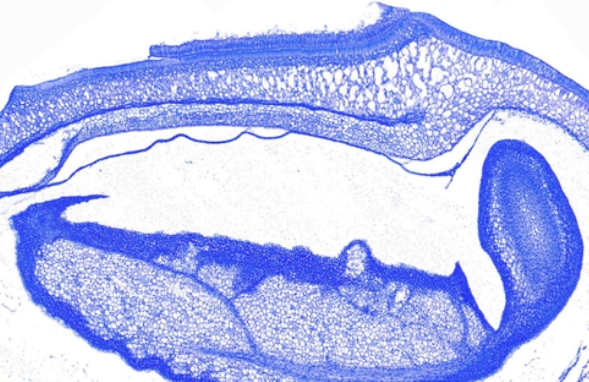

甲苯胺蓝染色又称为TB染色,这是一种常用的组织化学染色方法,广泛应用于生物学和医学研究中。甲苯胺蓝染色特别适合用于显示某些特定组织成分,如肥大细胞、软骨基质和神经组织中的尼氏小体等。